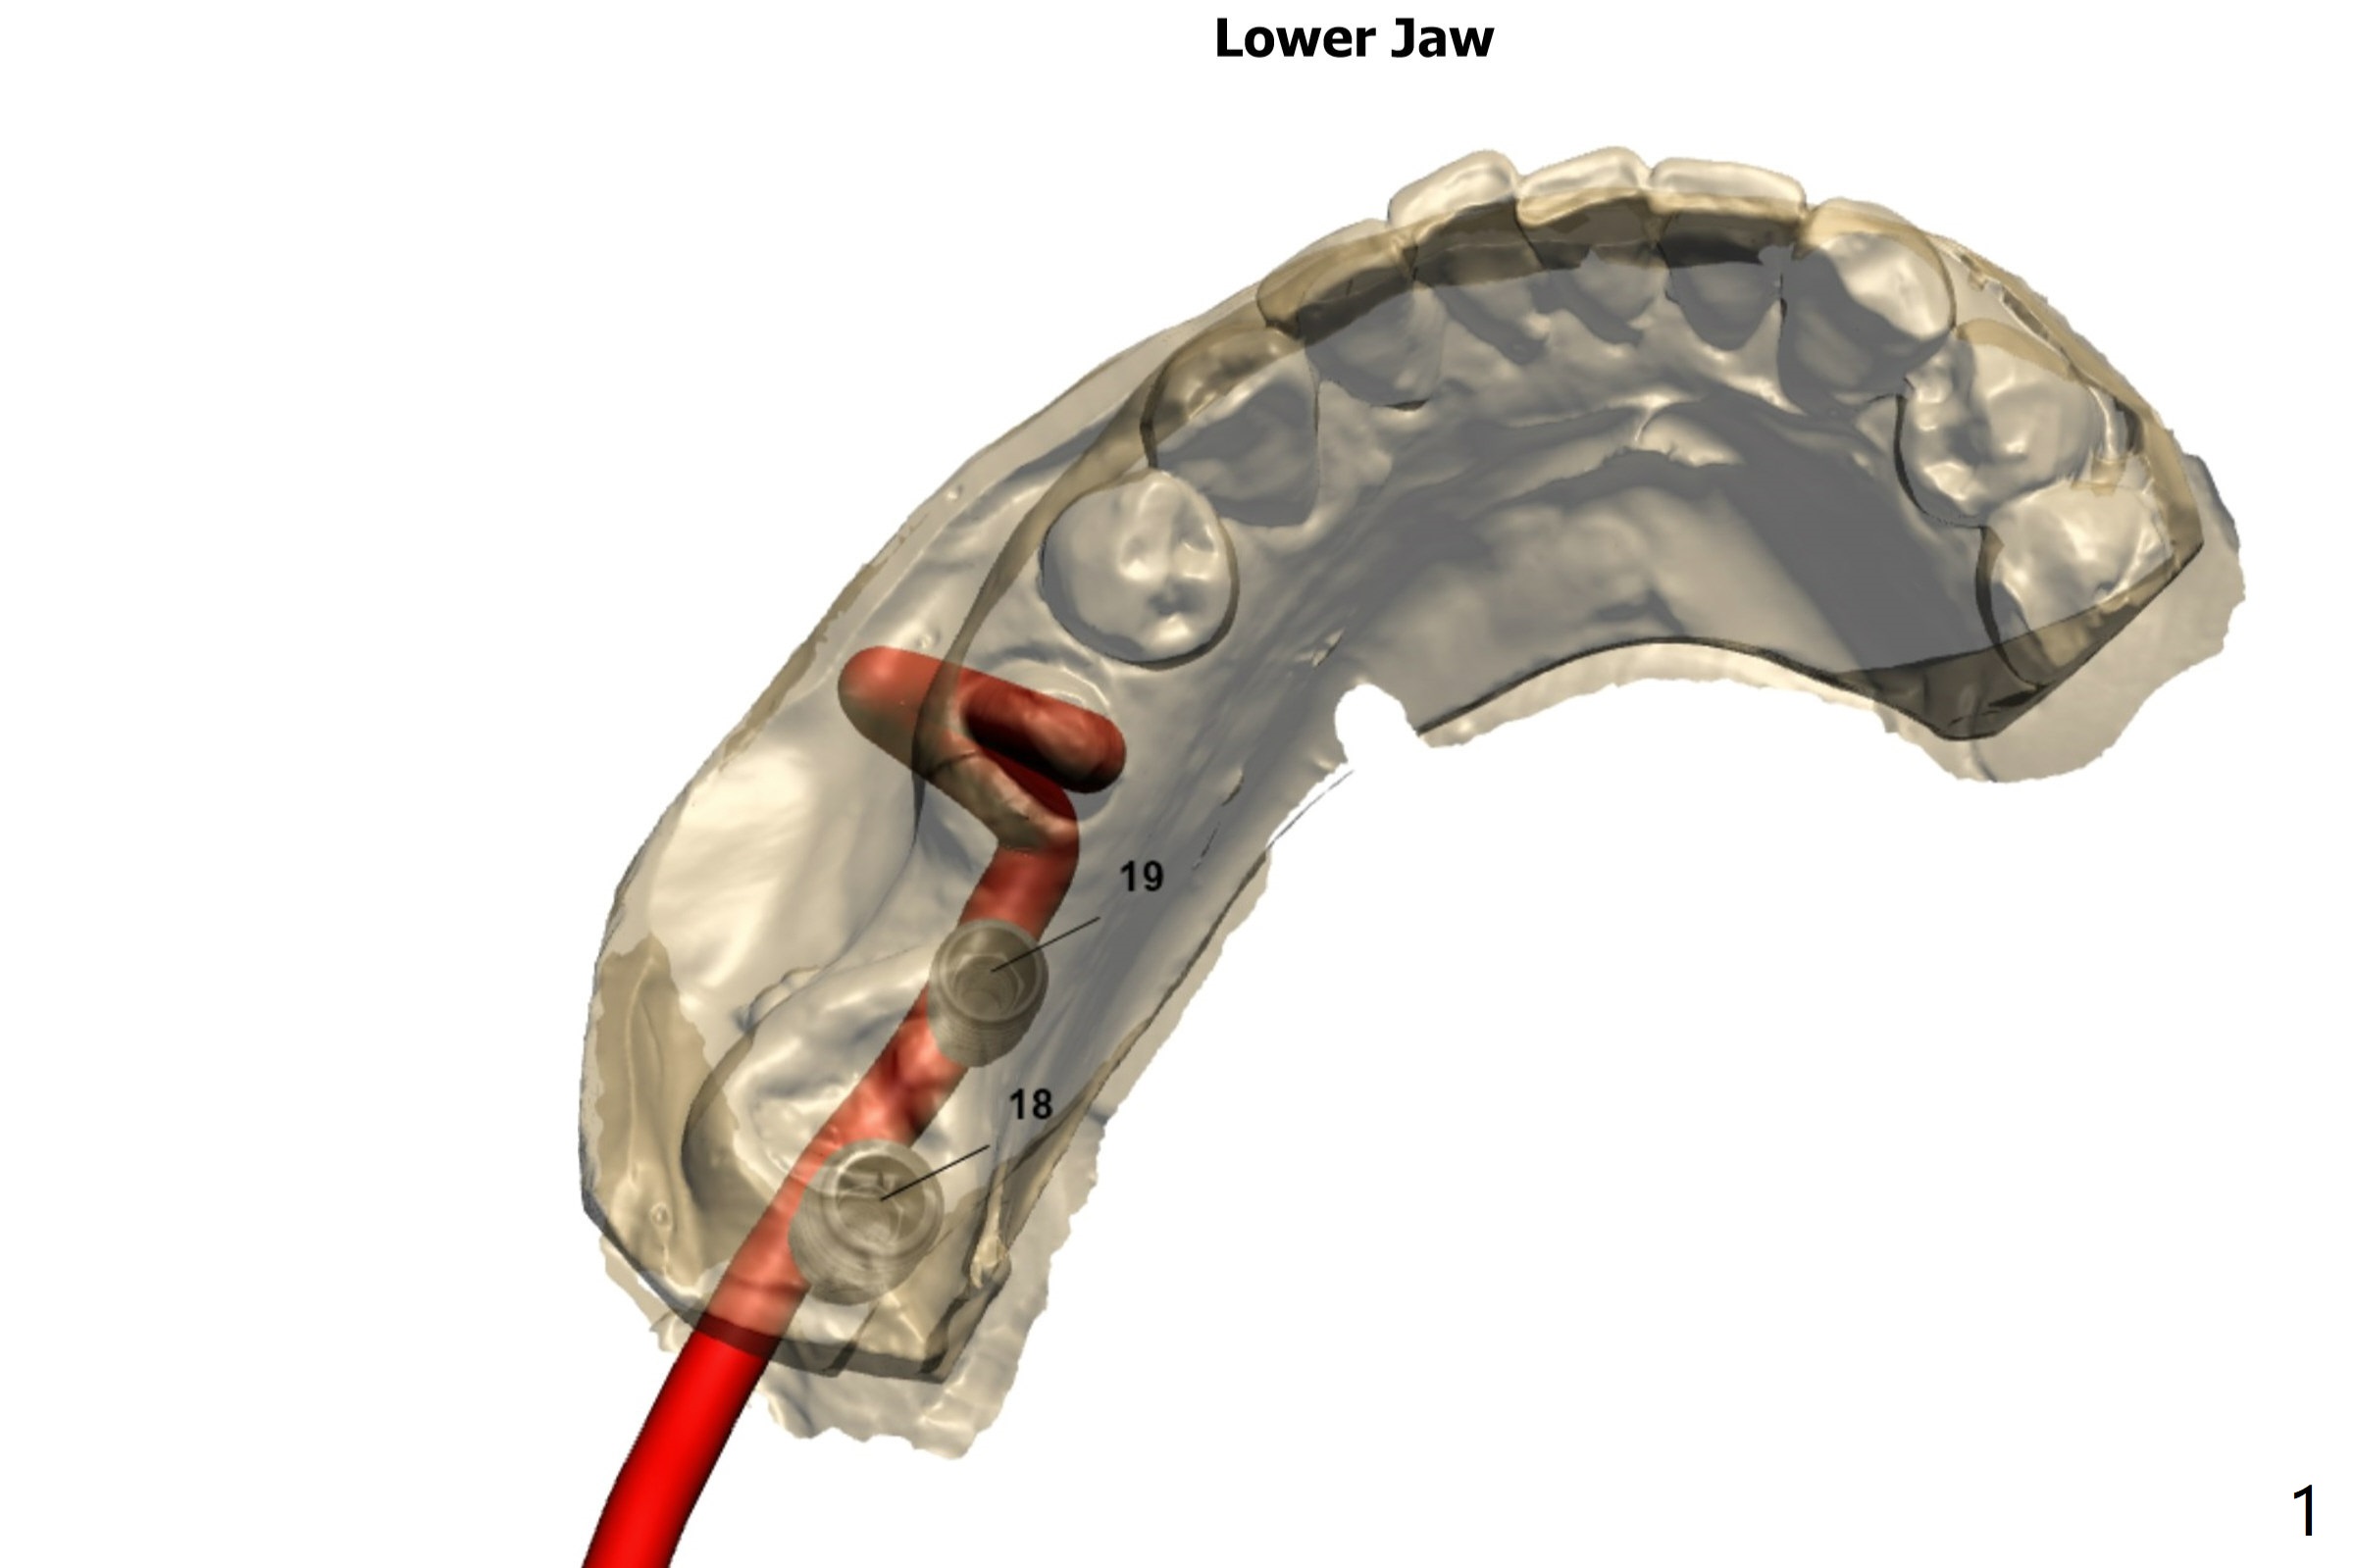

Use IS guide to place IBS implants at #18 and 19 (5x9 and 4x9 mm, respectively), to be consistent with #30. If fixture anchor does not work, use no stop fixture mount. In fact this is true.

Return to Lower Molar Immediate Implant, Prevent Molar Periimplantitis (Protocols, Table), Trajectory II, Metronidazole Xin Wei, DDS, PhD, MS 1st edition 07/11/2019, last revision 07/30/2019